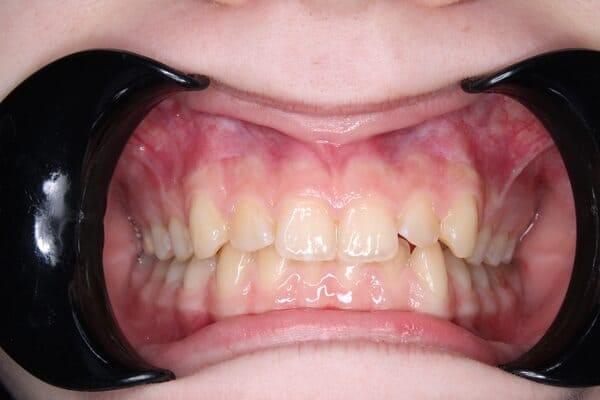

Видалення зубів мудрості – це важливий крок до гармонійної посмішки, особливо в підлітковому віці. Ми знаємо, що правильно обраний час для цієї процедури може запобігти багатьом проблемам в майбутньому.

Наявність зубів мудрості може призвести до серйозних ускладнень:

вони можуть заважати лікуванню брекетами чи елайнерами, а в деяких випадках – звести нанівець його результат. Саме тому ортодонт часто рекомендує їх видалити до початку чи під час лікування.